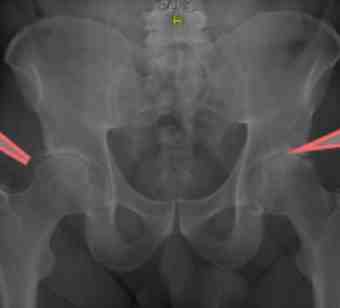

Notice the CAM deformities bilaterally, marked on your reading left, and the progressive arthritis, particular on the right.

This 55 year old man has had stiffness in both hips for many years. Three years ago pain began in the groins. Now he can barely get his socks on. He can't walk 9 holes on the golf course; he has to use the wagon.

In the xray above a CAM deformity is clearly seen. Below, closer inspection shows that he has in fact mixed CAM-Pincer deformity in this, his right hip; in fact in both. Moderate degenerative change is seen. An orthopaedic surgeon expects a bilateral hip replacement within two years.